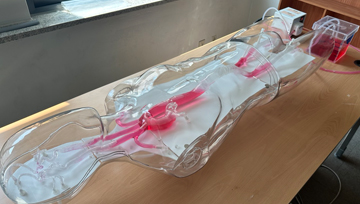

3) 3D 혈관 시뮬레이터 및 투시 조영술 X-ray

3D 혈관 시뮬레이터는 투시 조영술 X-ray 장비와 호환기능을 이용하여 최적의 영상을 시뮬레이션할 수 있습니다. 투시 장비를 이용하여 인체 모든 부위를 X-ray 영상으로 나타낼수 있습니다.

혈관중재시술에서 사용되는 가이드와이어, 스텐트, 코일 등은 3D 혈관 시뮬레이터를 통해 시연, 데모 될 수 있고, 학생들에게 직접 시뮬레이션할 수 있는 기회를 갖게 됩니다.

3D 혈관조영 시뮬레이터 또한 대학교 최초로 최신의 실습 장비로, 학생들에게 실제 임상에서 하는 진단 및 치료를 경험해 볼 수 있고 보다 이해도를 높일 수 있는 실습실입니다.